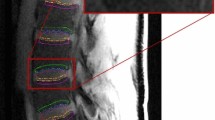

The data were processed as shown in the pipeline illustrated in Fig. 1. Before analysis, motion correction was performed on each DCE-MRI image series using 12-parameter affine transformation followed by nonlinear registration using FSL software tools (http://fsl.fmrib.ox.ac.uk/fsl/fslwiki/). Then, a trained operator manually drew regions of interest (ROI) on every slice of pre-contrast images of the DCE-MRI to segment out the 10 CEPs and SBs in the lumbar area (Fig. 2). We followed the guidelines described in previously published articles to outline those regions [18, 20]. ROI drawings were done on pre-contrast DCE-MRI images because the CEPs with short T2 relaxation remain visible in this particular pulse sequence with short TE. Therefore, these images provided more accurate delineation of the CEP regions, which would not be the case with conventional T1- or T2-weighted MRI images.

a Schematic diagram of IVD and adjacent vertebral bodies and ROIs. ROIs were named according to their positions relative to the adjacent IVD. b ROIs and corresponding projection planes (magenta straight lines) are shown for two different subjects. Note the subject-to-subject variations in the geometry of endplate surfaces

Spatial maps of DCE-MRI enhancement in SB and CEP regions

In order to generate spatial maps of DCE-MRI enhancement, the curved surfaces should be first projected onto a planar surface. The projection plane for each vertebral body surface was estimated by calculating the first and the second moments of the corresponding ROI. Using these moments, ROI’s center of mass and axis of orientation, which was defined as the direction of the axis with least inertia, were calculated [22]. Using these orientations, planes parallel to the cranial and caudal surfaces of each lumbar IVD were determined. A representative sagittal slice with projection planes (magenta line) is shown in Fig. 2b. Then, the DCE-MRI enhancement of each voxel within an ROI was calculated and projected onto the corresponding plane for each CEP and SB. Projections were calculated along the lines perpendicular to the surface (Fig. 4a). The length of the projection through each voxel is taken into account for proper normalization. All calculations were done using in-house code in Matlab (Mathworks, Natick, MA USA).

a Projection of voxel enhancement values onto a caudal plane and registration onto the template surface and mapping onto a representative vertebral body. b Schematic illustration of template surface generation using individual ROIs from healthy discs. The central region is shown with the magenta line and the peripheral region is the area between the magenta and the blue lines

In order to illustrate typical changes in spatial distribution of DCE-MRI enhancement with disc degeneration, one needs to average, for instance, all SB and CEP enhancement maps of grade IV discs. This requires that the anatomic variations between subjects as well as variations across all lumbar levels should be taken into account. Therefore, we generated a template of the surface between the disc and the vertebral body and spatially normalized each individual CEP and SB surface projections onto this template. The template was generated from the SB and CEP ROIs of subjects with healthy discs (grades I or II across all lumbar levels). Overall, data from 21 subjects were used for the template (age 30 ± 9 years, 9 females, height 171 ± 10 cm, weight 71 ± 12 kg, BMI 24.3 ± 3.7 kg/m2). To generate this group template, first the center of mass was estimated for each individual surface. Then, the distance from the center of mass to the edge of the surface was calculated along radial lines with 1° increments (Fig. 4b). First, this was done for each lumbar level separately (dotted lines in Fig. 4b) and then these templates were averaged using the same process to obtain one single template (blue solid line in Fig. 4b). Then, each CEP and SB enhancement map was spatially registered to this template as shown in Fig. 4a.

We further separated the SB and CEP ROIs into central and peripheral regions to study the different enhancement characteristics we have seen in these regions. The area between the blue and magenta lines in Fig. 4b is defined as the peripheral region (54 % of the total surface area), and the area inside the magenta line is the central region (46 % of the total surface area). The boundary is defined heuristically based on the spatial enhancement characteristic seen in healthy endplates.